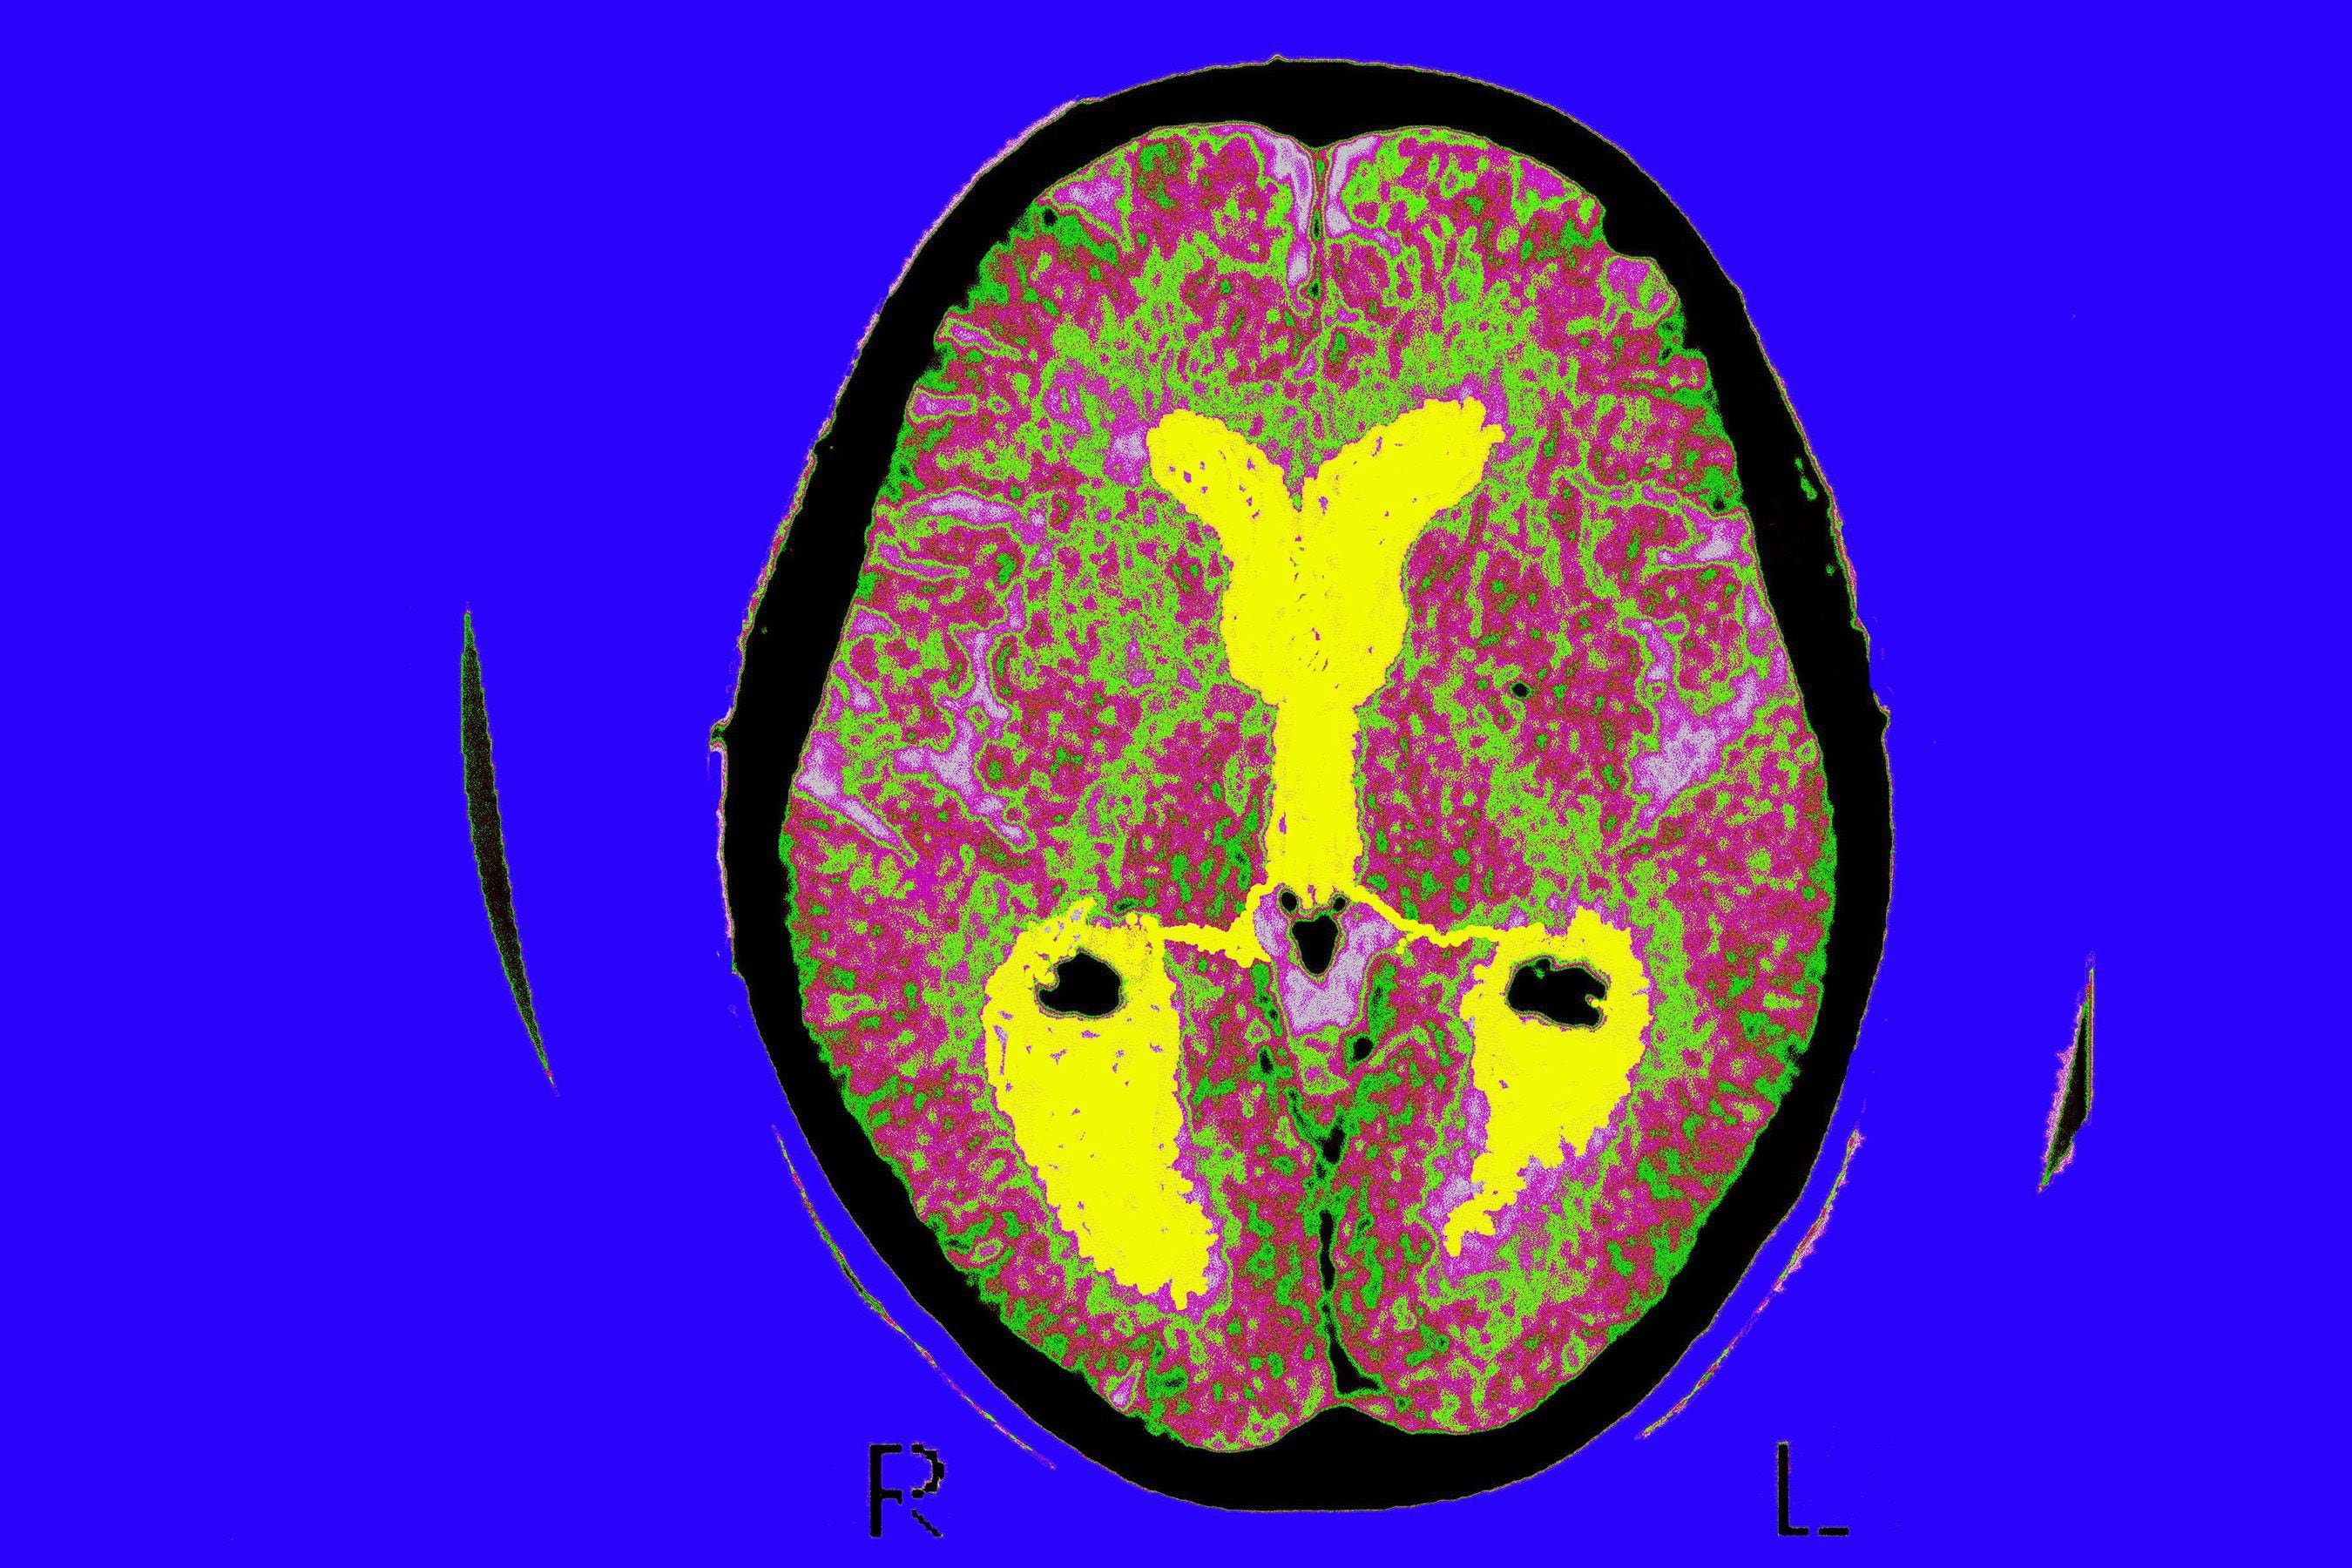

La EA cambia todo el cerebro, provoca la muerte de las células nerviosas y la pérdida de tejido en todo el cerebro. Con el tiempo, el cerebro se encoge drásticamente, lo que afecta a casi todas sus funciones. Si bien factores relacionados al estilo de vida -como la dieta, el sedentarismo o el hábito de fumar- influyen en el riesgo de desarrollar Alzheimer, entre el 60% y el 80% de los casos tienen una base genética.